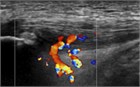

1. ジャンパー膝はジャンプやランニング動作を繰り返すスポーツ選手に好発する膝蓋腱近位部のスポーツ障害である。

1. ジャンパー膝の場合、超音波画像検査を行う事が推奨される(推奨度1)